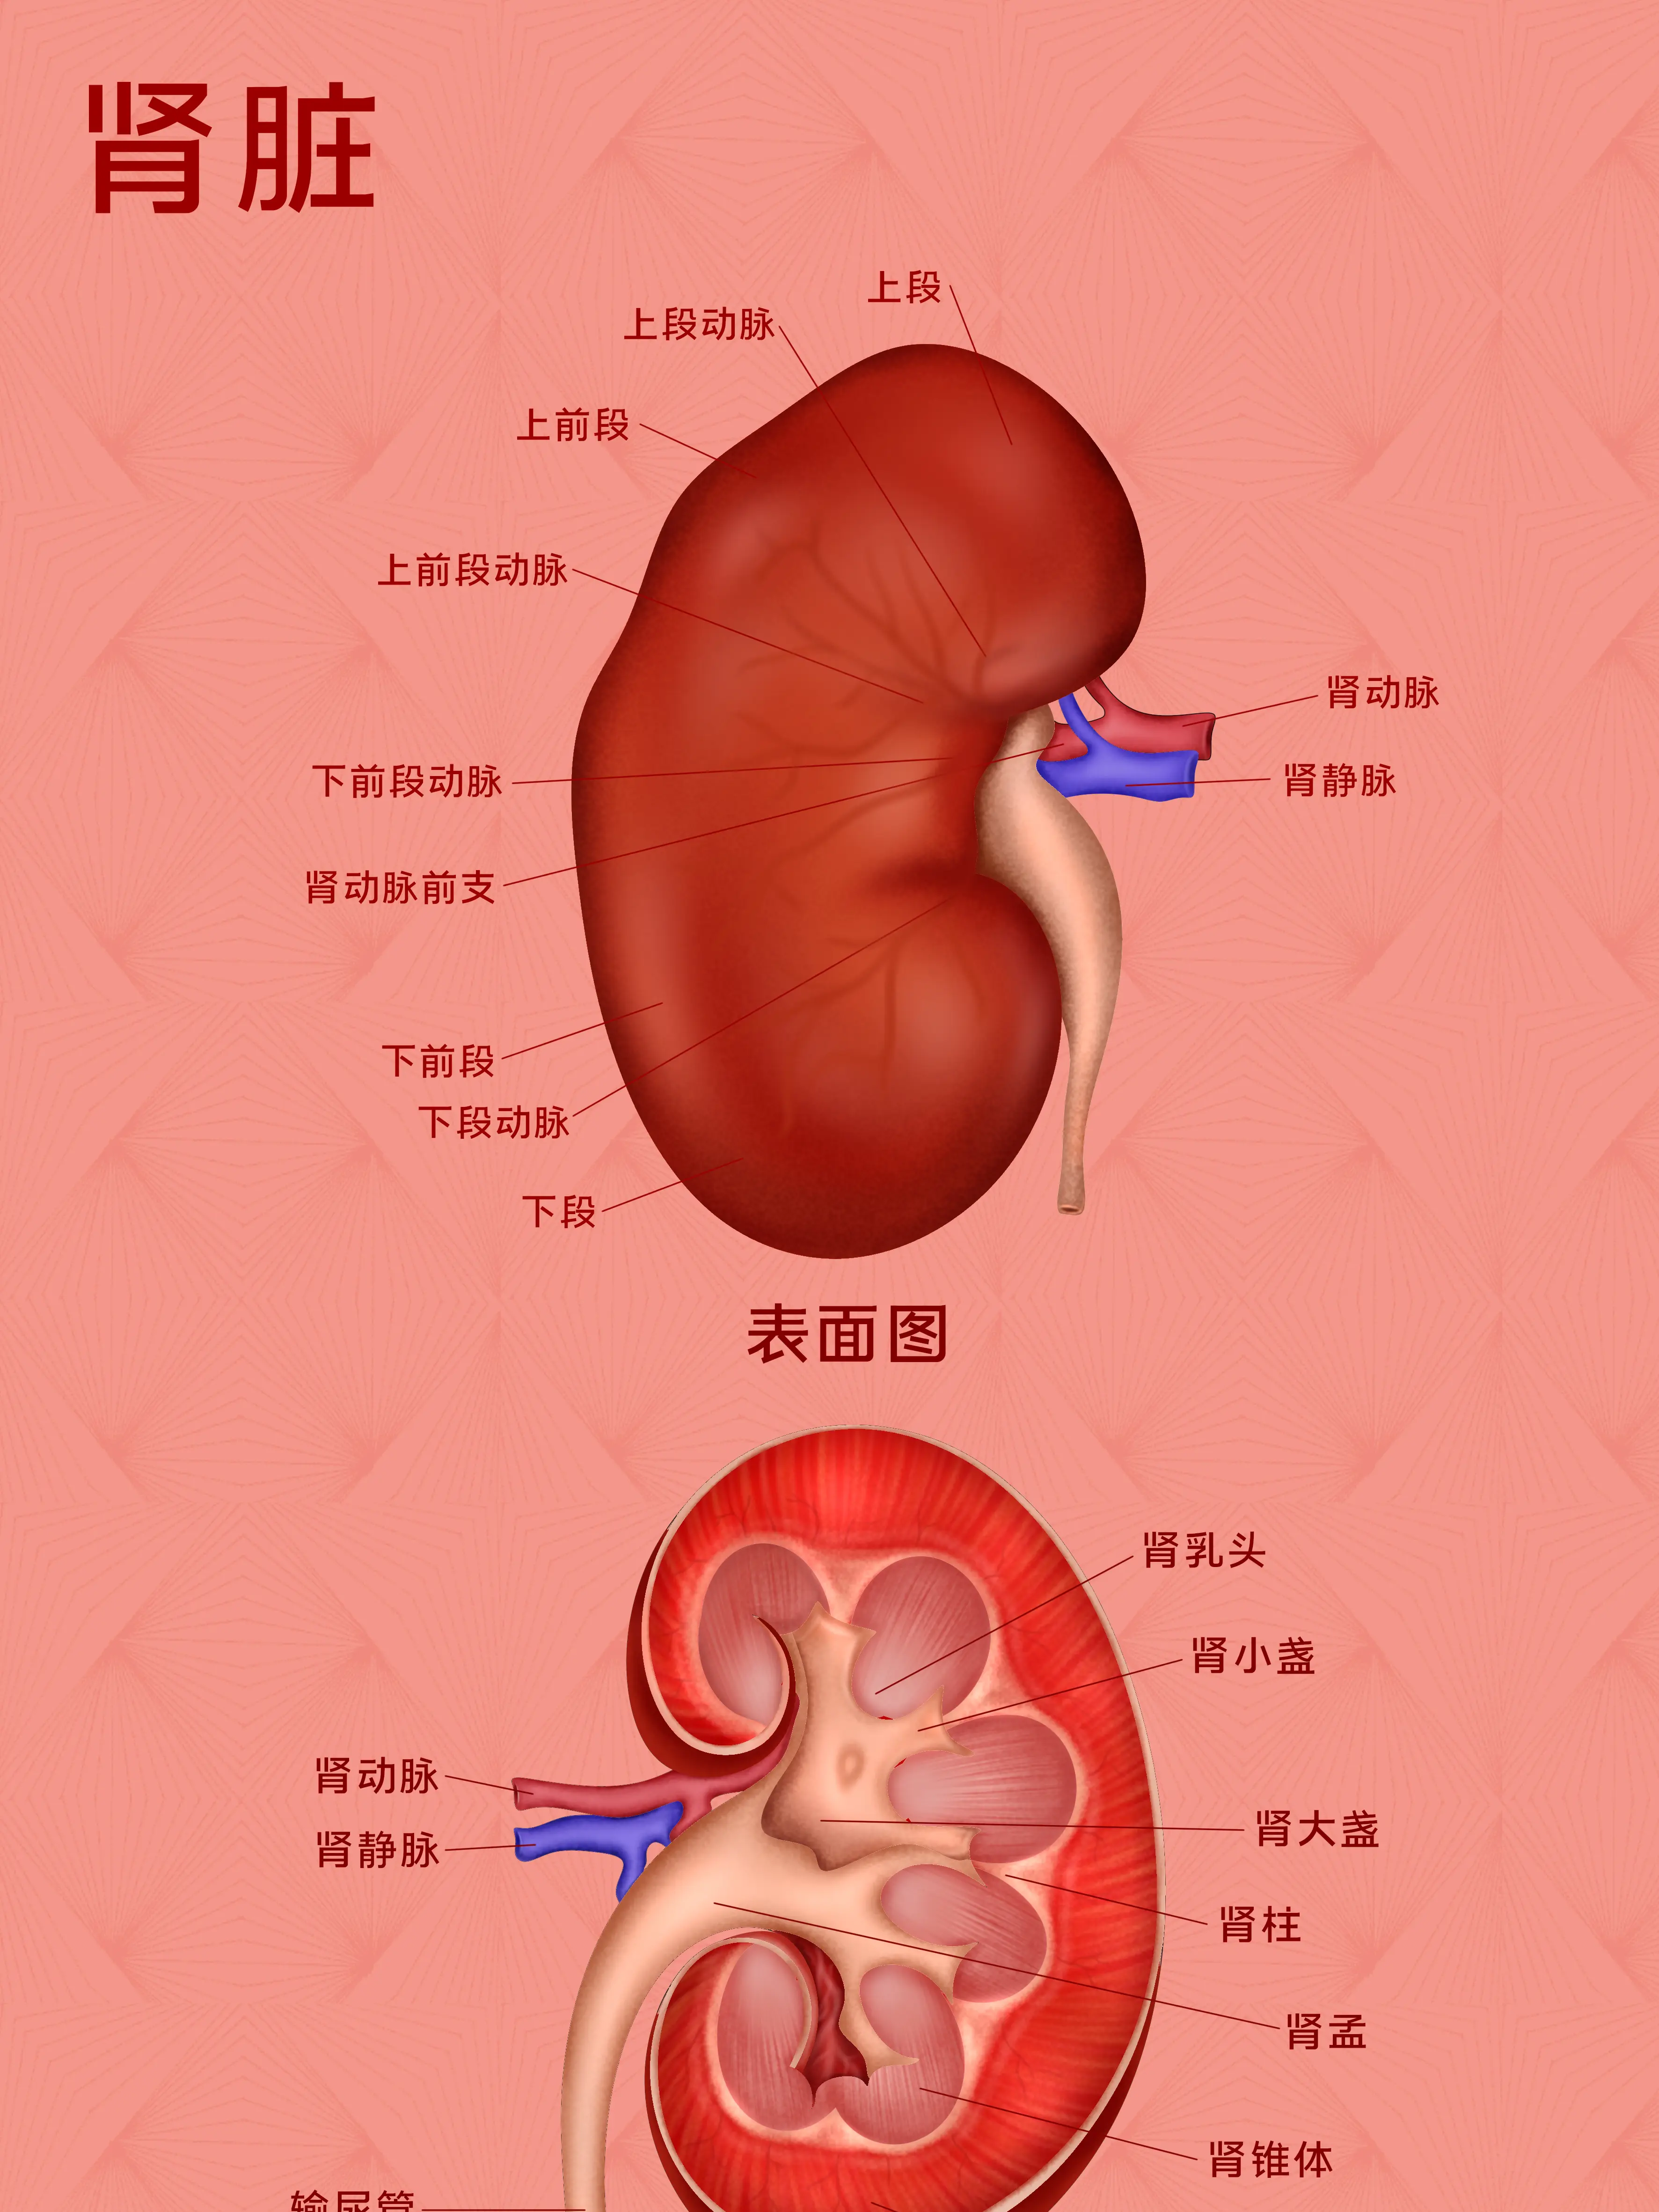

人體身上的器官科普,可以更好的了解自身的身體情況...

醫學醫療知識科普...

人體身上的器官科普,可以更好的了解自身的身體情況...